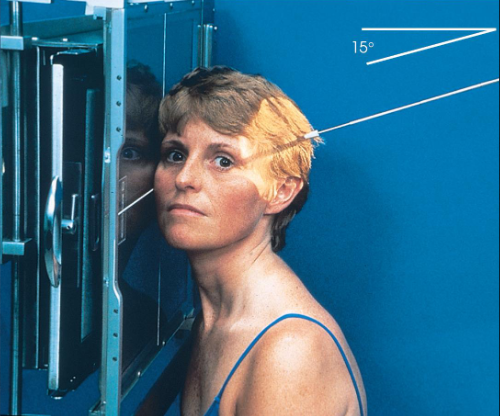

Axiolateral (modified Schuller) TMJs

patient position:

right or left lateral, both sides done for comparison

semiprone or upright

part position:

center ½ inch anterior to the EAM to the IR

head in true lateral

MSP parallel with IR

IPL perpendicular

one exposure with the mouth closed, and a second with the mouth open (if not contraindicated

respiration suspended

CR:

25-30 caudad

enters ½ inch anterior and 2 inches superior to upside EAM

collimation:

1 inch betond the anterior skin line, posteior and inferior to the TMJs